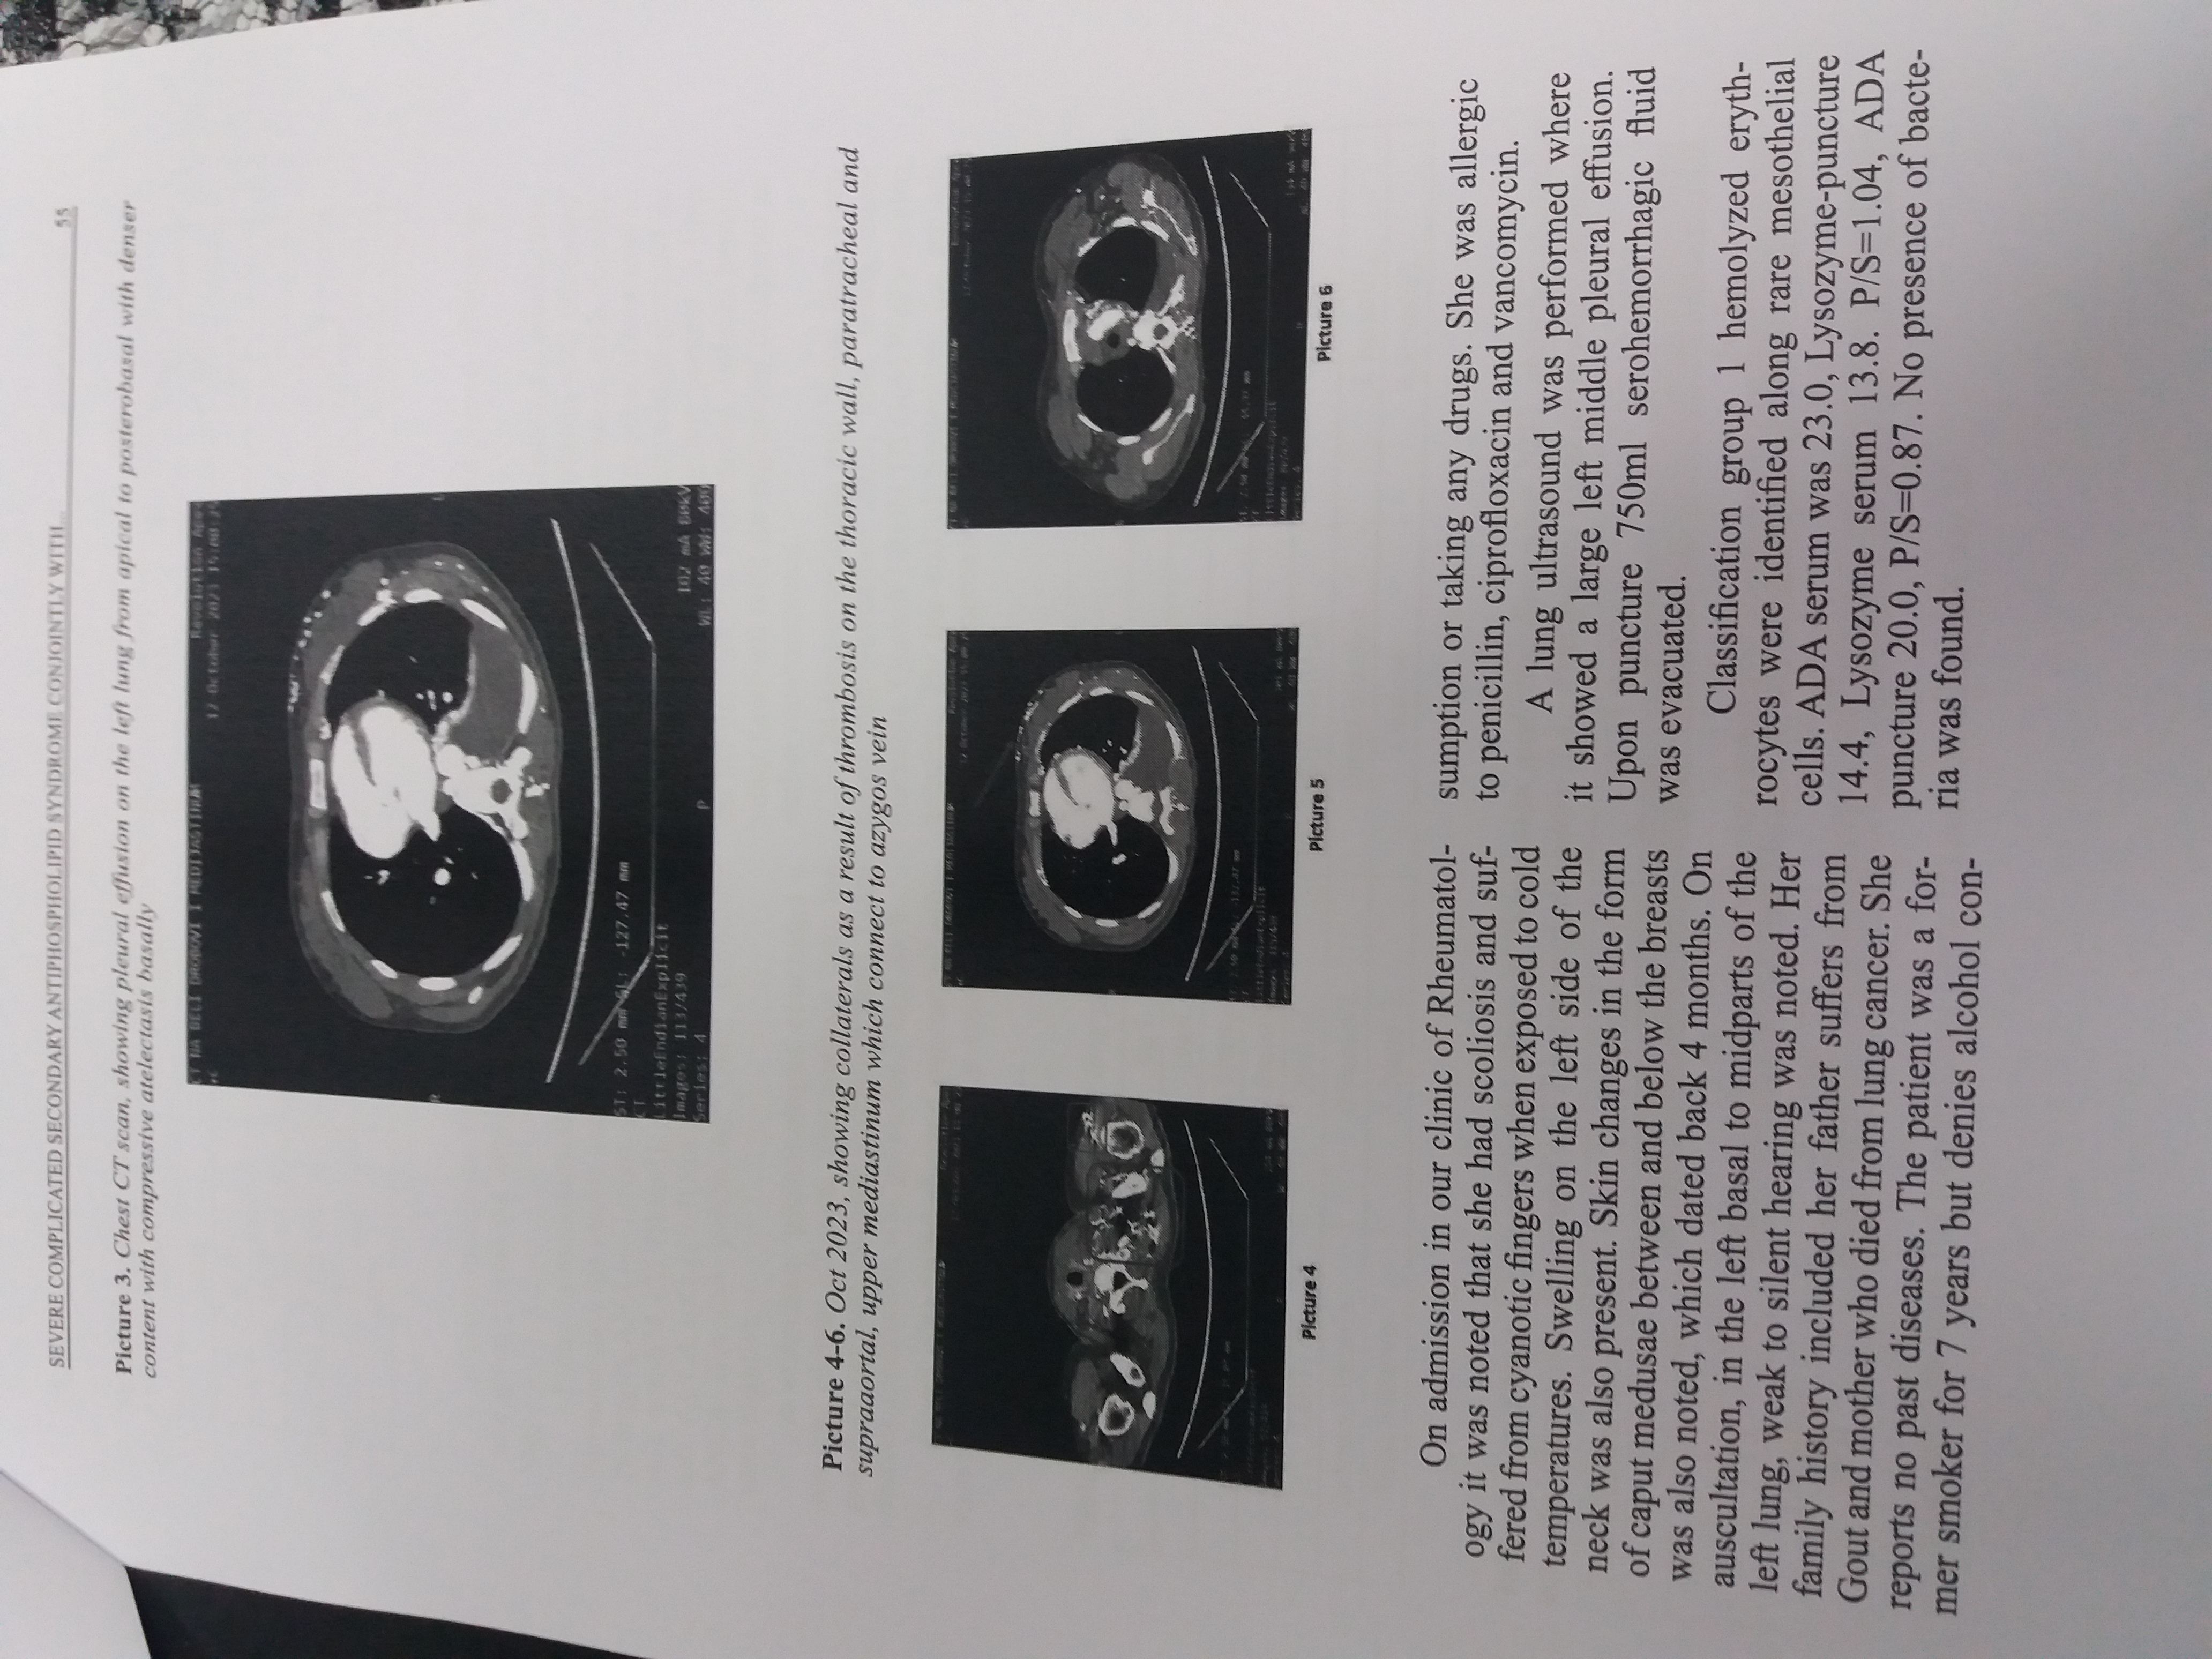

Antiphospholipid syndrome (APS), is an autoimmune systemic disorder known to manifest with thrombosis in almost all vessels throughout the body, can also be accompanied by pregnancy morbidity, and is persistent with the presence of antiphospholipid antibodies, including lupus anticoagulant antibodies, or relatively high titers of anticardiolipin, or anti-β2Glycoprotein I antibodies. APS can occur alone or in association with other diseases, more commonly systemic lupus erythematous. In patients with both underlying diseases episodes of arthritis, skin changes in the form of livedo reticularis, thrombocytopenia and leucopenia were more common. Cardiac manifestations have also been reported. Here we present a complicated case of a young female patient with antiphospholipid syndrome and an underlying systemic lupus erythematosus.